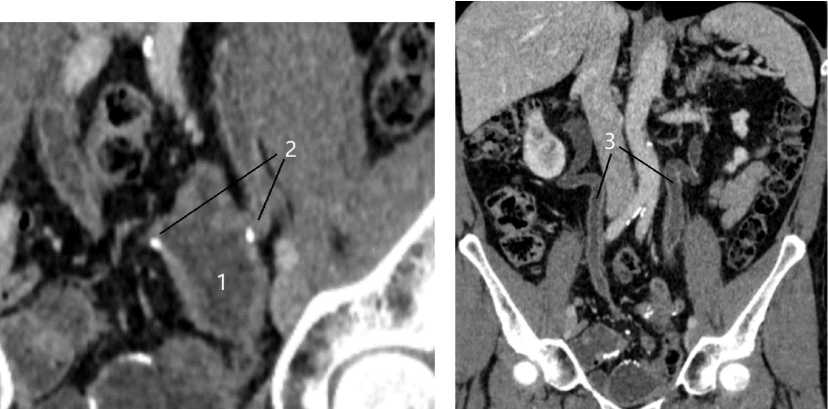

В течение двух лет пациент не появлялся на амбулаторном приёме нашего центра до появления текущих жалоб. По данным обследования, выявлены повторные стриктуры УИА (рис. 1). Учитывая длительный анамнез пациента, рецидив стриктур обоих УИА, нами было принято решение о выполнении оперативного вмешательства в объёме лапароскопической реимплантации мочеточников к мочевому резервуару с использованием периоперационной ICG-флуоресценции мочеточников в режиме ангиографии.

Рис. 1. Предоперационная КТ в режиме урографии — билатеральная стриктура УИА: 1 — ортотопический резервуар по Штудеру; 2 — стриктуры УИА; 3 — билатеральный гидроуретер

Fig. 1. Preoperative CT urogram — bilateral stricture of UIA: 1 — orthotopic neobladder (Studer); 2 — UIA strictures; 3 — bilateral hydroureter